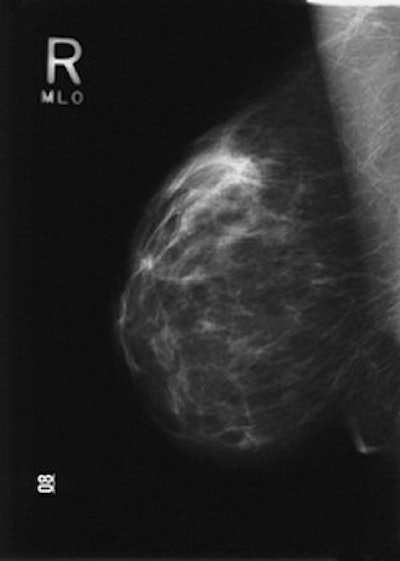

MLO images of the left breast in one patient. With (a) MC and (b) BC, the inframammary fold (open arrow) is depicted. A larger amount of the whole breast is depicted in b, on the basis of the positions of the three calcifications (arrowheads) and the round opacity (*). In addition, a cutaneous fold (solid arrows) is present in the axilla in a. Sardanelli F, Zandrino F, Imperiale A, et al, "Breast biphasic compression versus standard monophasic compression in x-ray mammography," Radiology 2000; 217:576-580.